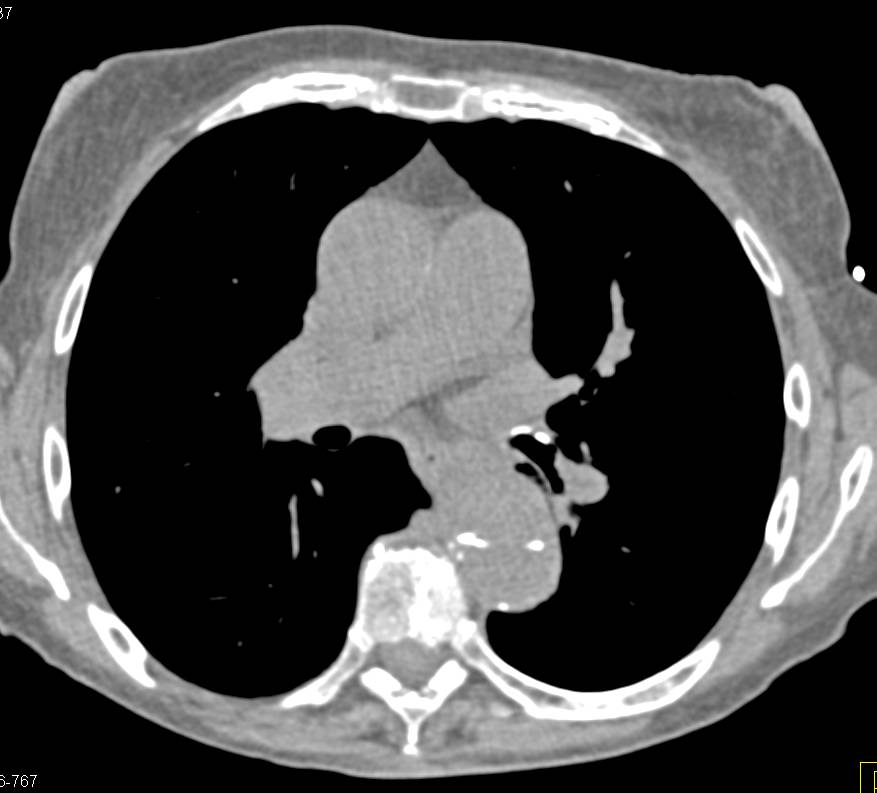

Diagnosis

Normal Superior Mesenteric Artery (SMA) on MIP View